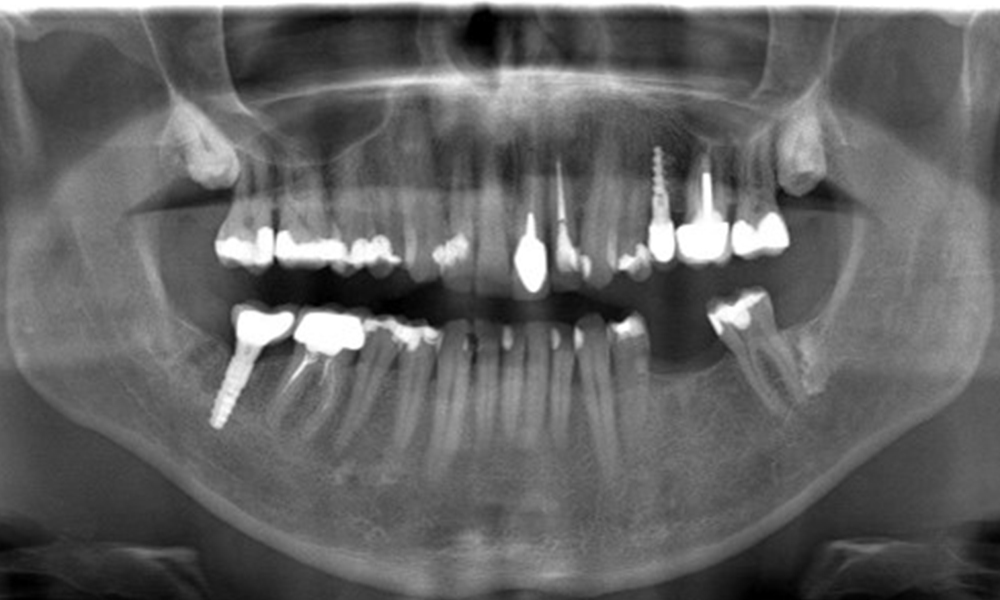

In the medical history, the 55-year-old patient states that he has no systemic disease and is not taking any medication. The patient’s lifestyle is similarly unremarkable. The patient has a few tooth restorations and two implants (2nd and 4th quadrants). On the basis of current findings, gingivitis is identified in an otherwise stable periodontal condition on the reduced periodontium (stage III, grade A).

Previous treatments: dental restorations (non-precious metal/ceramic blend), two implants (2nd, 4th quadrants)

OPG: 29/02/2024